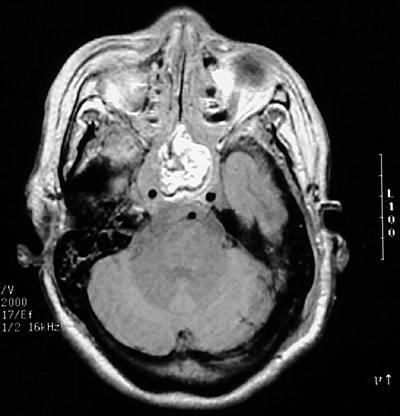

The region of the clivus (sella turcica) has a large destructive mass seen with T1 weighted MRI scan above and with gadolinium contrast in coronal and axial views below. This is a chordoma.